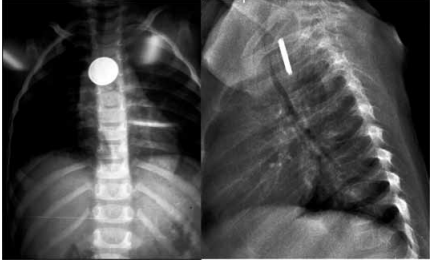

Menina de 3 anos, há uma hora, engoliu um corpo estranho enquanto brincava sozinha em seu quarto. Ninguém

presenciou a ingestão. Desde então, apresenta disfagia,

sem sialorreia e sem nenhum outro sintoma. As radiografias de tórax realizadas estão apresentadas na imagem

a seguir.

A conduta é: